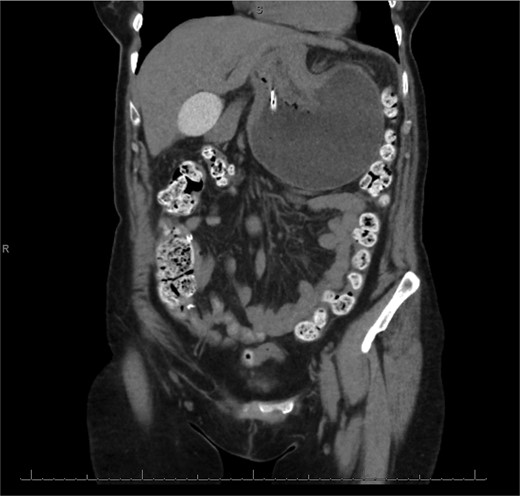

The patient was a 74-year-old female with a history of hypertension, chronic migraines, hiatal hernia repair with Nissen fundoplication repair, and cecal volvulus treated with right hemicolectomy who presented with abdominal pain, nausea, and vomiting. Six months prior, she exhibited symptoms of bloating and nausea, which were treated with oral Reglan with some improvement. She reported vomiting episodes for 2 months that acutely worsened over the 4 days prior to presentation. Examination revealed a soft and mildly distended abdomen with tenderness in the epigastrium and left upper quadrant. Initial vital signs showed a temperature of 36.1°C, blood pressure of 149/88 mmHg, heart rate of 115 beats/min, and oxygen saturation of 95% on room air; tachycardia resolved with resuscitation. Labs were notable for a white blood cell count of 8.8 × 1000/mcL and hemoglobin of 14.2 g/dL. Sodium was 137 mEq/L, potassium was 3.3 mEq/L, and creatinine was 0.75 mg/dL. Computed tomography (CT) of the abdomen and pelvis (Figs 1 and 2) showed gastric volvulus without pneumatosis, significant wall thickening, or distention. Nasogastric tube was placed. An upper gastrointestinal fluoroscopy scan showed no passage of contrast beyond the stomach and demonstrated 90° rotation of the stomach (see Fig. 3). The patient underwent surgery that same day.

Sagittal view of CT scan of abdomen and pelvis demonstrating gastric volvulus.